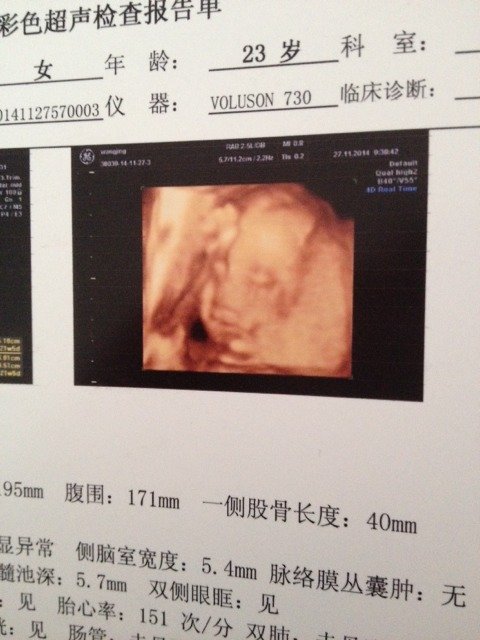

大家帮忙看下我刚刚做的四维彩超 这张图片宝宝是睡着了吗宝宝是睡着了吗 大家帮忙看下我刚刚做的四维彩超 这张图片宝宝是睡着了吗宝宝是睡着了吗 点击展开 静静宝贝 2014-12-11 10:43 为您推荐: 其他回答 你好,这个也不能说明孩子就是睡着了呢,胎儿字母体内这个姿势是很正常的 青丝弯弯月 2014-12-11 17:47 好清楚,我的不清楚 原来的我_hO10 2014-12-11 12:29 都是这样的, 乐乐妈咪… 2014-12-11 12:08 都是这样的 晴晴是伟伟的老婆 2014-12-11 11:03 这B超非专业人士都看不懂的 136*****373_pc0z 2014-12-11 10:54 加载更多 相关问题 今天去做了四维彩超,请问这张图片能看的出宝宝是闺女还是儿子吗?孕25+3那么害羞,呵呵呵 四维彩超有一张图片上面有日期,那个日期是什么意思啊 急!!!请大家帮忙!请有关人士帮我看下这张图片是男宝宝还是女宝宝?